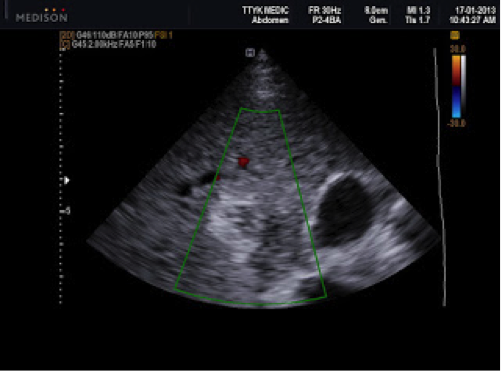

Bệnh nhân nữ 24 tuổi, chậm kinh 2 tuần, nghi có thai nhưng siêu âm tử cung không thấy túi thai trong tử cung hoặc khối cạnh tử cung.

Siêu âm phát hiện ở gan có ổ tròn đậm âm, kích thước 1,86cm, ở giữa có dịch.

Xét nghiệm β-hCG: 34.000 IU/L.

CT: có một ổ trong gan gần túi mật kích thước 2cm, ở giữa khối có dịch (giảm âm), được cung cấp máu từ động mạch gan.

Chẩn đoán thai dưới gan. Điều trị tiêm MTX, sau 2 tuần, xét nghiệm β-hCG trở về bình thường, không cần can thiệp ngoại khoa. Kết quả tốt do phát hiện sớm (Phan Thanh Hải và cs., 2007).